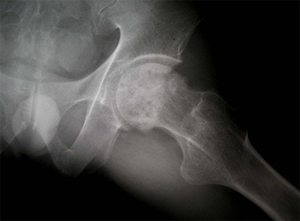

• 수술 전 고관절 X-선 수술 전 고관절 X-선 사진

상기 환자는 46년 전부터 고관절 통증이 있었으며, 12년전 Lt. total hip replacement(THR)을 받은 분으로 2년 전부터 통증으로 인해 물리치료를 받았지만 통증이 지속되었고, 본원 OS 외래에서 방사선 촬영하여 Lt. THR loosening 소견으로 revision O.P. 위해 입원하여 O.P.이후 재활위해 물리치료실로 의뢰됨